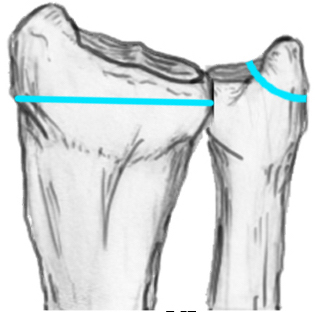

Radial angles

| Volar tilt mean 11° | Radial inclination mean 22° | Radius mean 11 mm longer than ulna |